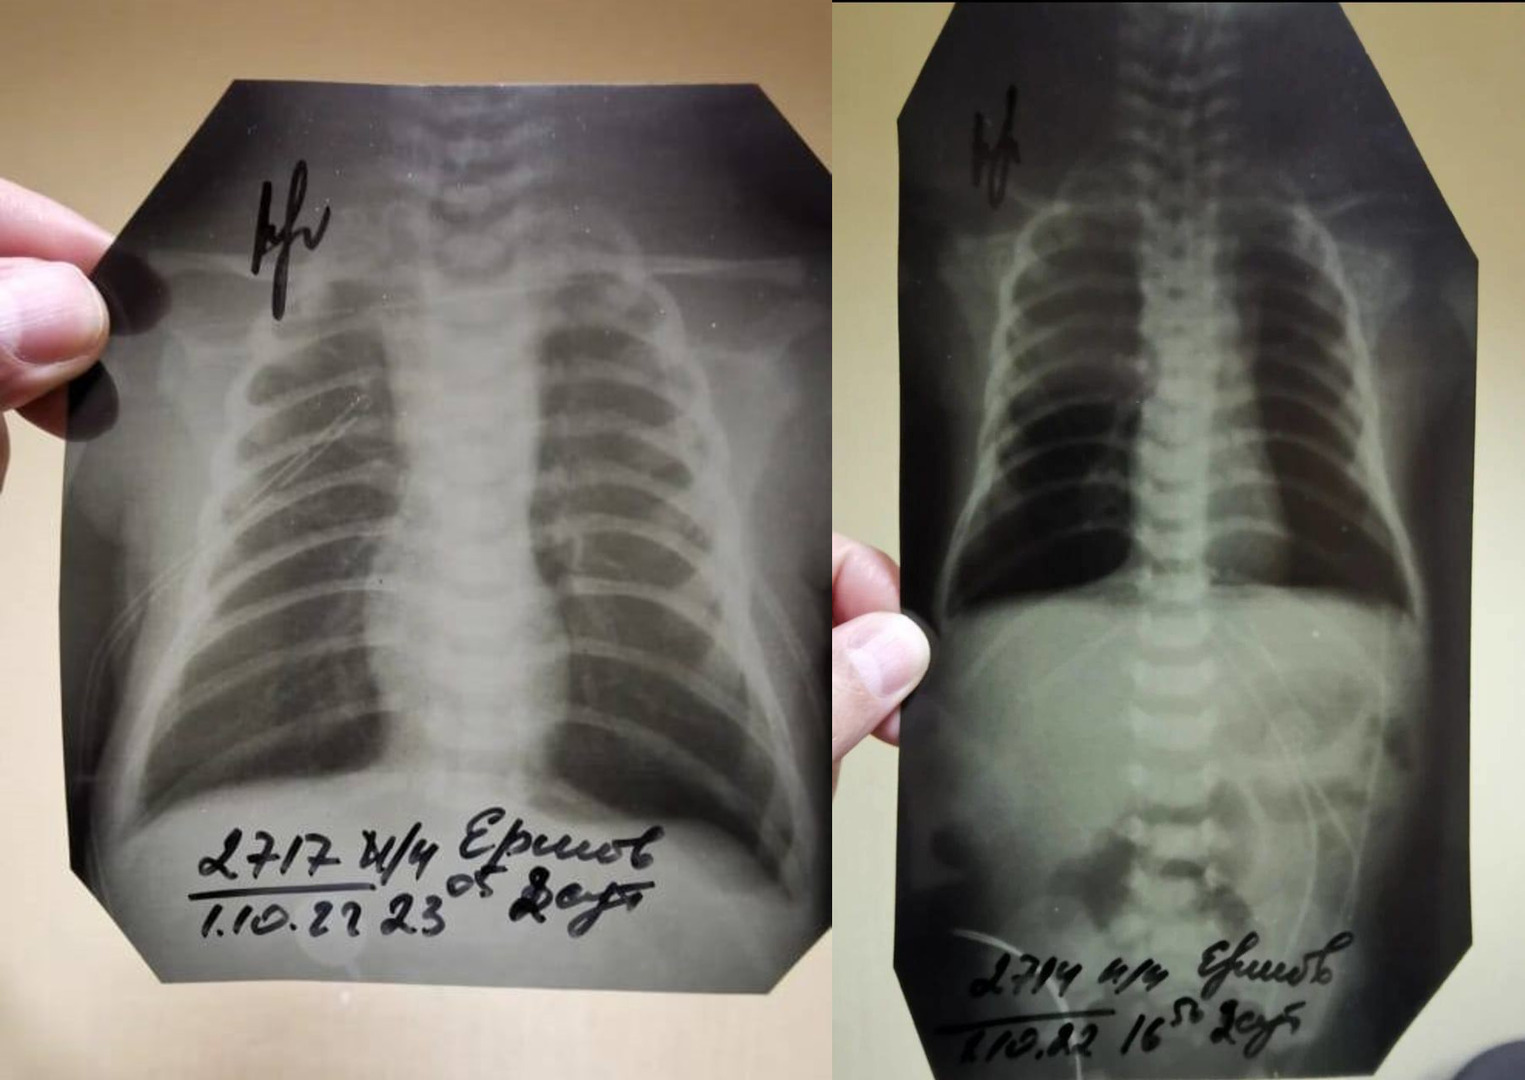

Отцу также препятствуют в ознакомлении материалов дела, заявляет сам Ершов. Странности в уликах тоже есть — например, если в прошлом году следователи говорили, что рентгеновские снимки были утеряны больницей, то после жалоб их вдруг нашли, как утверждает отец. Только есть одна деталь — место, в котором обычно аппарат печатает ФИО пациента, врача, проводившего рентген, дату и время процедуры, было вырезано на всех снимках. («Страсти» ознакомились с результатами рентгена).

«Все эти данные обрезаны. Видно, что обрезали это ножницами или чем-то ещё, криво, косо. И просто обычным маркером подписано: Ершов В. Д. Мой сын. А вместо ФИО врача, который проводил процедуру, просто стоит подпись. Интересно, что каждый снимок делался в разные дни и в разное время, а подписи стоят на всех 21 снимках одного и того же врача. Он что, один работает без выходных?», — добавил он.

Сам Ершов считает, что снимки, которые внезапно нашлись, на самом деле не принадлежат его ребенку.